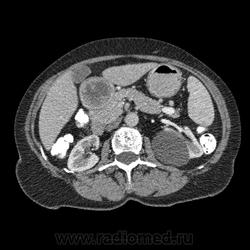

Впечатление, что дуля эта вне головки п.ж., интрамурально в луковице, что ли... тогда возможно GIST, но надо дайком. Утолщение подслизистой в антральном отделе желудка, не удается проследить переход от желудка к 12-перстной((. Внутрипросветно/внутристеночно - не разобрать. 1 фаза?

Клинику! Есть ли признаки высокой тонкокишечной непроходимости, что при ФЭГДС в 12-перстной - туда удалось пройти или нет? ААА! Одни вопросы))))

В-общем, варианты такие без дайкомов: пролапс слизистой в 12перстную, безоар, внутрипросветный дивертикул, гастроинтерстинальная опухоль. И большие сомнения, что это в головке п.ж. - оно отделено от неё тонким слоем жировой клетчатки

Фаз было 3. Видео не выставлял прошлый раз пришел ответ из сайта что видео не работает на сайте Идет накопление контраста в нативе в центре +2+4 по периферии +32+34 .в артериальную +20 и +65 +70 соответственно.

Что оно копит - бог с ним... если это пролапс слизистой, то суммация стенок. Безоар бы не копил. Напрягает отек слизистой в антрале... Это должно быть скорее внутри просвета кишки, т.к. оттесняет газ в 12-перстной на периферию. Без дайкомов больше ничем не могу, извините. Подождём мнения коллег.

Как мне видится - пролапс слизистой желудка в 12-перстную. А мнения коллег что-то нетути...

А что растет из левой почки? Может оно же и желудок сдавливает?

Это расширение всей 12- перстной кишки (стаз).